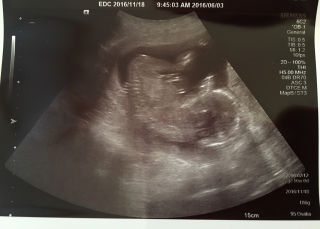

写真:16w0d:りんさん

全身うまく写りました。15週から胎動を感じるようになり、可愛くてたまらなくなりました。無事健康に産まれますように。早く会いたい!!性別はわからないみたいですか、なんか付いてるような、、、

BPD36.6mm、推定体重129gとのこと(*^^*) 性別はまだ分からないと言われましたが、順調だそうでなによりです! エコー中は手をグーパーしたり、お顔を隠したりとっても可愛かったです(*´ω`*)

初めての妊娠です! 1ヶ月前よりも倍以上の大きさに成長してました! 頭からお尻まで9㎝足は2.5㎝でした☆大きさも週数通りで順調とのこと! 多分男の子かな~?来月まで保留だね~!と言われました☆ よーく見るとおしゃぶりをして口をもぐもぐさせていて、とても可愛いかったです。 はっきり分かる胎動は14週頃からありました! 日に日に胎動が強くなり今ではぐるぐる回る感じやキックをしてお腹が動いているのが目に見えるぐらいの強い胎動になりました!動くたびに可愛くて話しかけてます!主人もお腹が動く度に喜んでいて、それをみて私はほっこり幸せを感じています☆

今日は寝ていましたが、ムニャムニャと体勢を変える仕草がとても可愛かったです。背骨がくっきり見えて、人間らしい曲線が出来ているのに感動しました。 BPDも3.7cmで順調とのこと。性別は次回かな~楽しみです。